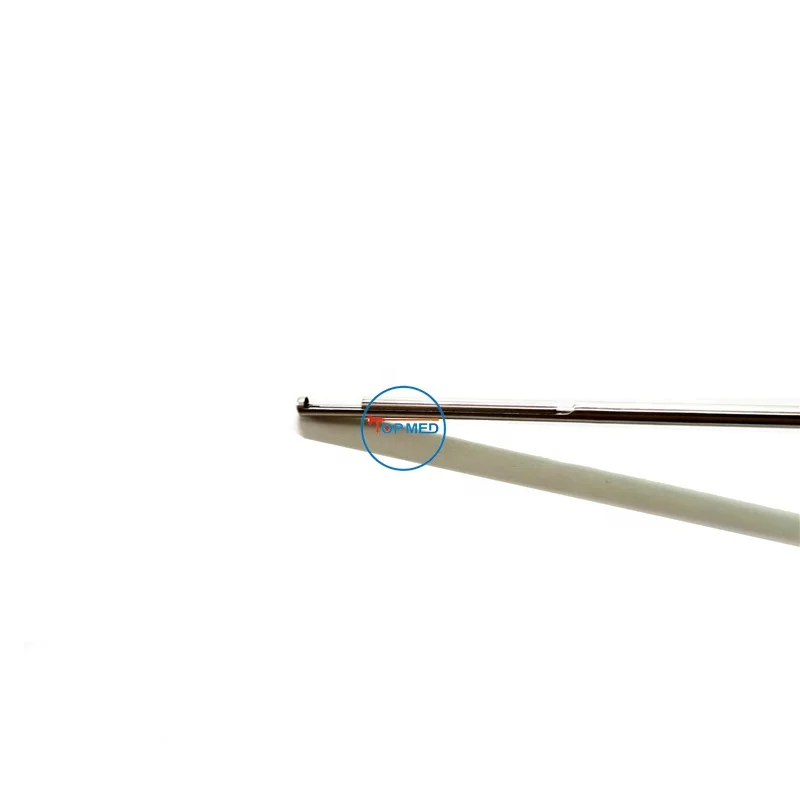

2.5*330mm foreign body grasping forceps flexible serrated forceps transforaminal endoscope spine endoscope

- Category:

- Supplier: Top,(hangzhou),E-Commerce,Co.,Ltd.

$200.00 - $215.00

In Stock